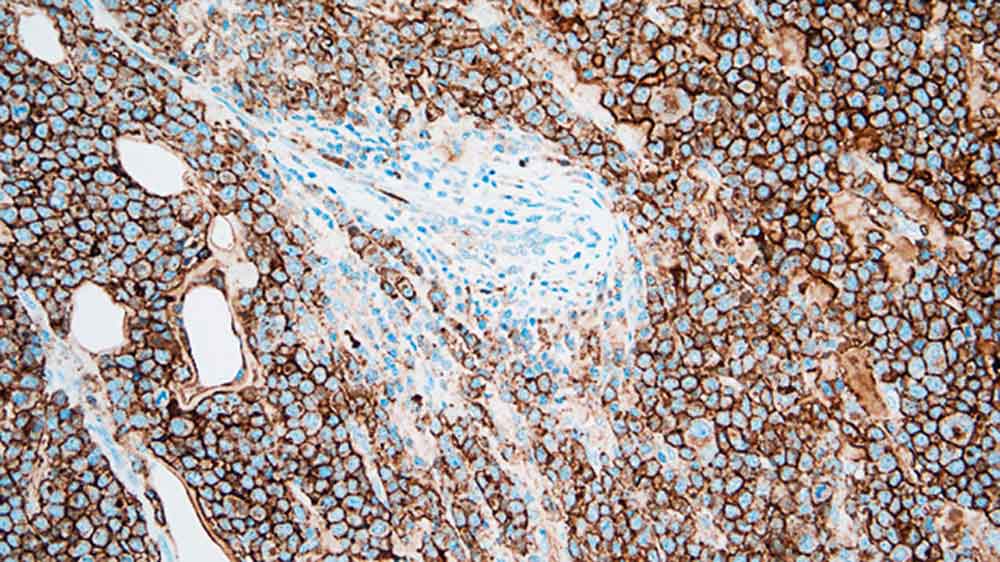

The CD138 molecule is a transmembrane heparan sulphate glycoprotein expressed at distinct stages of differentiation in normal lymphoid cells such as pre-B cells, immature B cells and Ig-producing plasma cells as well as being expressed in stratified and simple epithelia. The loss of CD138 expression from atypical cells is reported to be an early event during cervical carcinogenesis whereas CD138 antigen expression shows a close association with preserved epithelial morphology and differentiation; however, the major utility of CD138 as a marker in immunohistochemistry is the quantification of plasma cells.

CD138 (Syndecan 1) is recommended for the detection of specific antigens of interest in normal and neoplastic tissues, as an adjunct to conventional histopathology using non-immunologic histochemical stains.